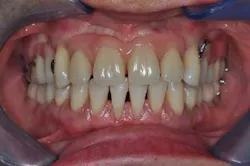

Figs. 8a, b, c, and d: Final results

Figs. 9a, b, and c: Two years’ postop. Note the patient’s commitment to maintaining an optimal oral hygiene